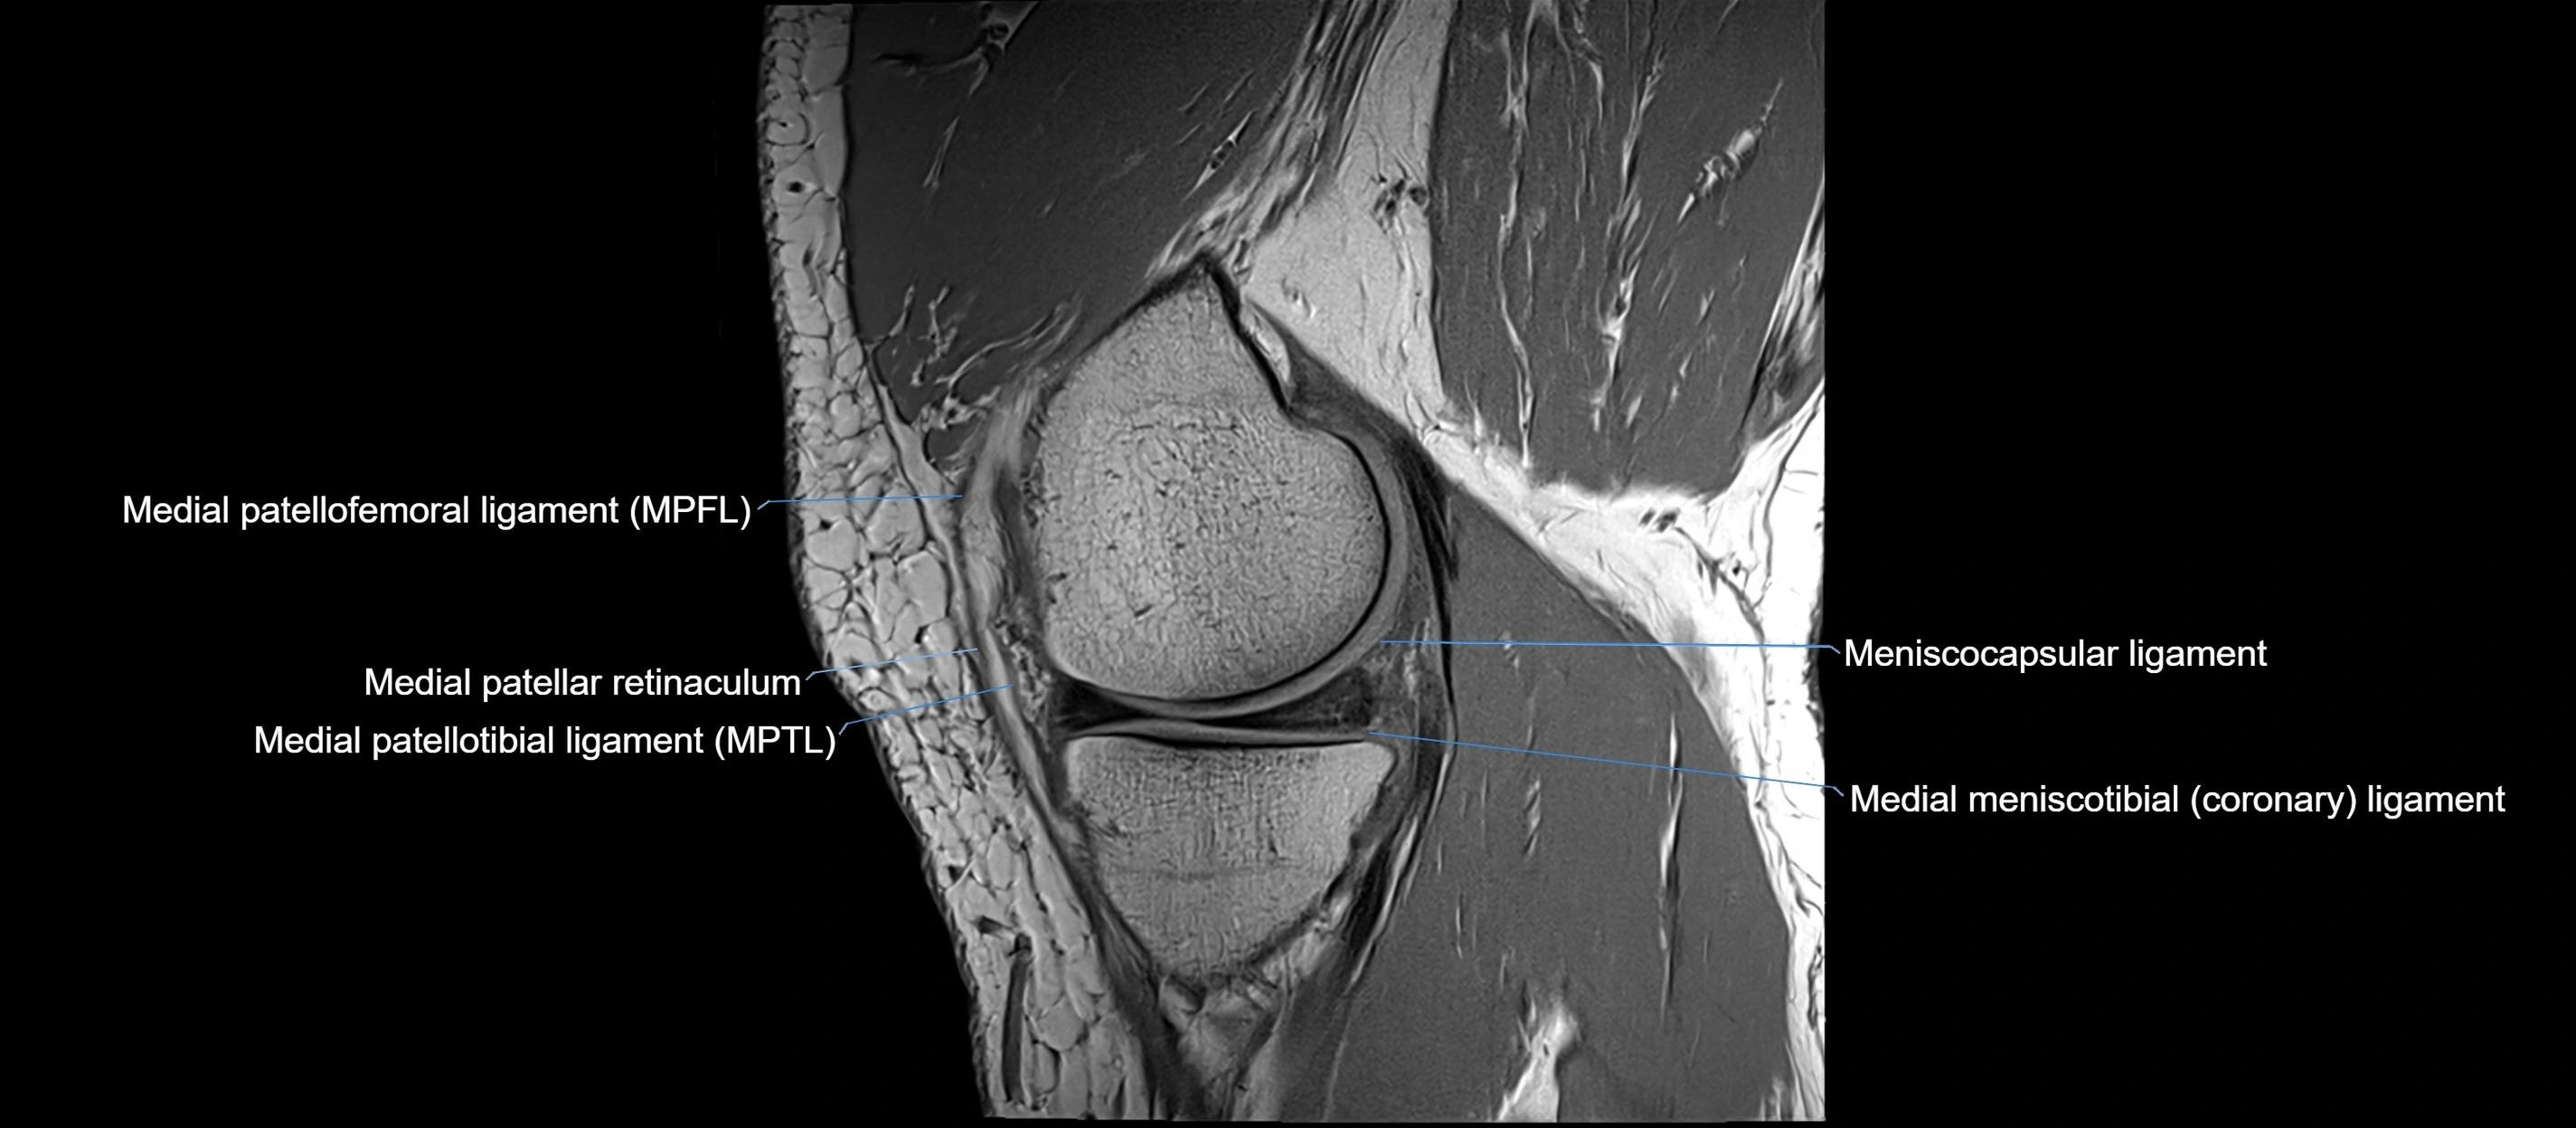

MRI images

image